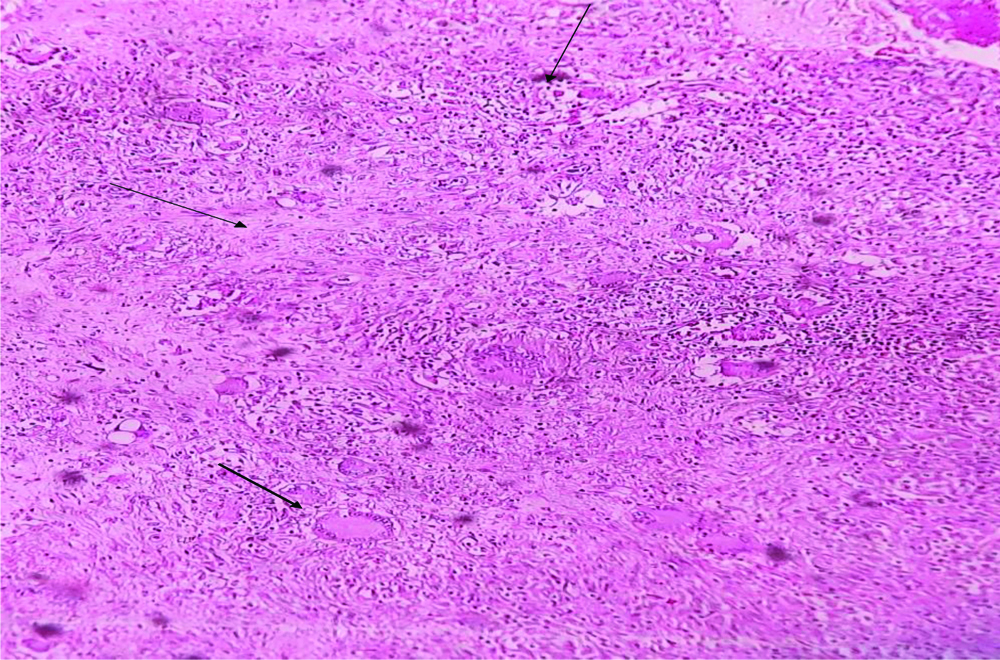

The patient was clinically diagnosed with L1-L2 spondylodiscitis, Koch’s/metastasis with L5-S1 spondylolisthesis with bilateral radiculopathy. He underwent D10-S1 posterior instrumentation with stabilisation with discectomy [Table/Fig-2d]. Biopsy and exudate sample sent for routine laboratory investigations. AFB culture were positive for Mycobacterium tuberculosis complex and also were confirmed by CBNAAT which was sensitive to rifampicin. Histopathological Examination (HPE) of L3-L4 spine tissue showed caseating TB [Table/Fig-3].

Histopathological Examination (HPE) of spine tissue showing granulomas with areas of caseation necrosis, epithelioid cells, Langahan’s, and foreign body giant cells H&E,10X.

In this series, after obtaining informed and written consent debridement with posterior instrumentation with stabilisation by using titanium material was performed on the patients. Microbiological investigations of spinal TB were made with tissue/exudate conventional TB culture and CBNAAT [13]. One of the cases of HPE revealed caseating TB inflammation. Spinal TB once diagnosed by clinical and radiological ATT should be empirically started as early as possible before the aetiological diagnosis is confirmed. Duration of treatment remains controversial due to difficulty in assessing the response and risk of relapse, so most experts recommend 9-12 months of treatment [8]. In these cases, as there was no neurological deficit/impairment ATT was given for 12 months.